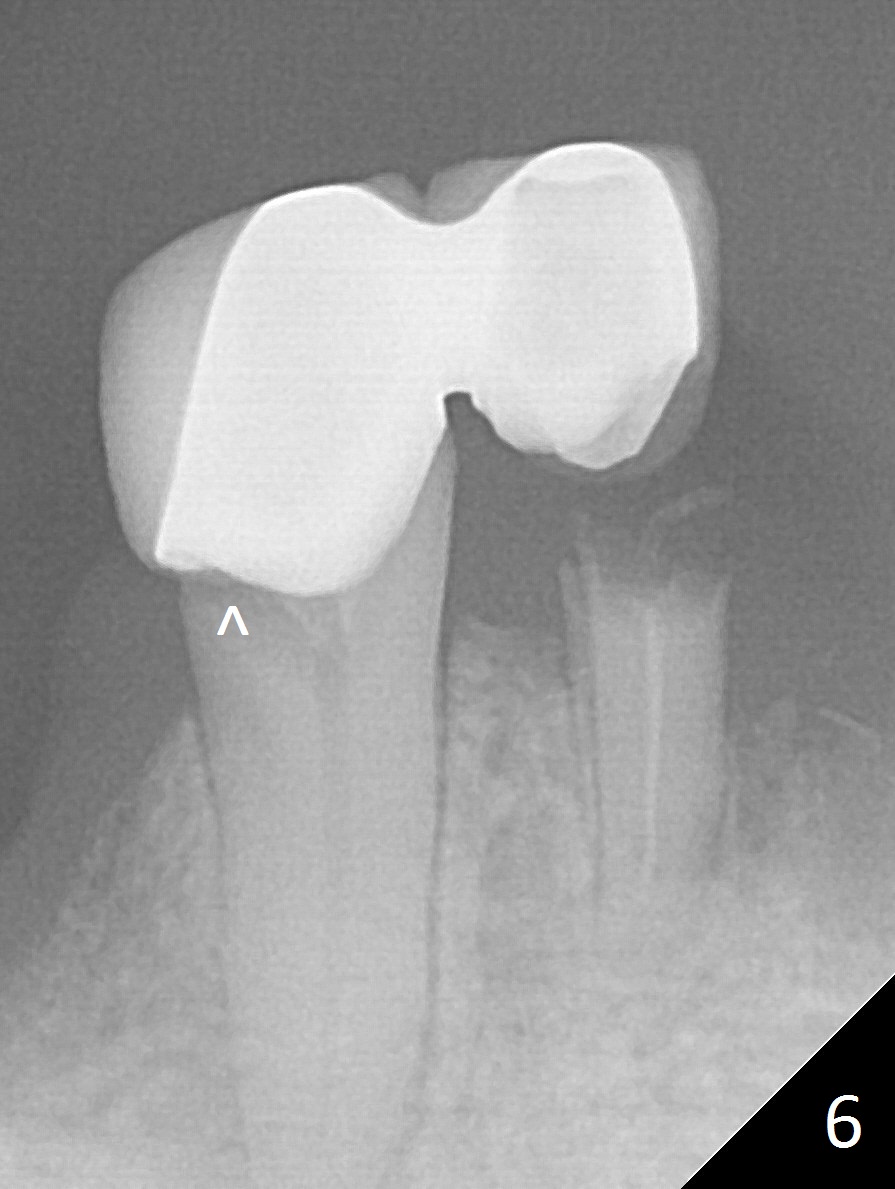

A 62-year-old woman has poor dentition (Fig.1). The most critical area is the upper left anterior: #9-11, which were extracted 4 months earlier (Fig.2). Implants will be placed at #9 and 11 with fabrication of a provisional bridge (Fig.3). After incision, use Magic Split to start bone expansion, followed by micro-osteotomes 1 and 1.5 mm and Magic Osteotomes 3 and 3.8 mm. If the transition between 1.5 and 3 mm osteotomes is not smooth, apply RT2. Place the smallest bone-level implants (for hybrid denture in the future) with gold coated abutments. There should be no interference with or without the partials and in and out. Next step should be removing splinted crowns at #26 and 27 (Fig.1), RCT for #27 and immediate implant at #26 (Fig.5,6 Metronidazole). In fact the splinted crowns at #26 and 27 were lost last week. The patient thinks that she needs 2 implants. The next one is to remove the crown at #5 for RCT (Fig.4).